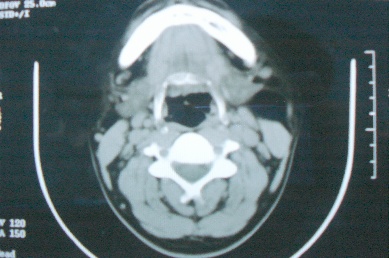

ct10755,男,28岁。发现左侧腮腺区肿块几年,今要求ct检查。左侧腮腺区低密度影,ct值-153hu。

左侧腮腺区囊状低密度影,ct值-153hu,考虑腮腺脂肪瘤。

病灶为一边界清晰脂性区,其内未见实质性组织.支持考虑:左侧腮腺脂肪瘤可能性大.

ct能定性的良性肿瘤不多,对脂肪瘤的诊断是比较有把握的,加大窗宽还可以看到里面有分隔

ct值-153hu,腮腺脂肪瘤。